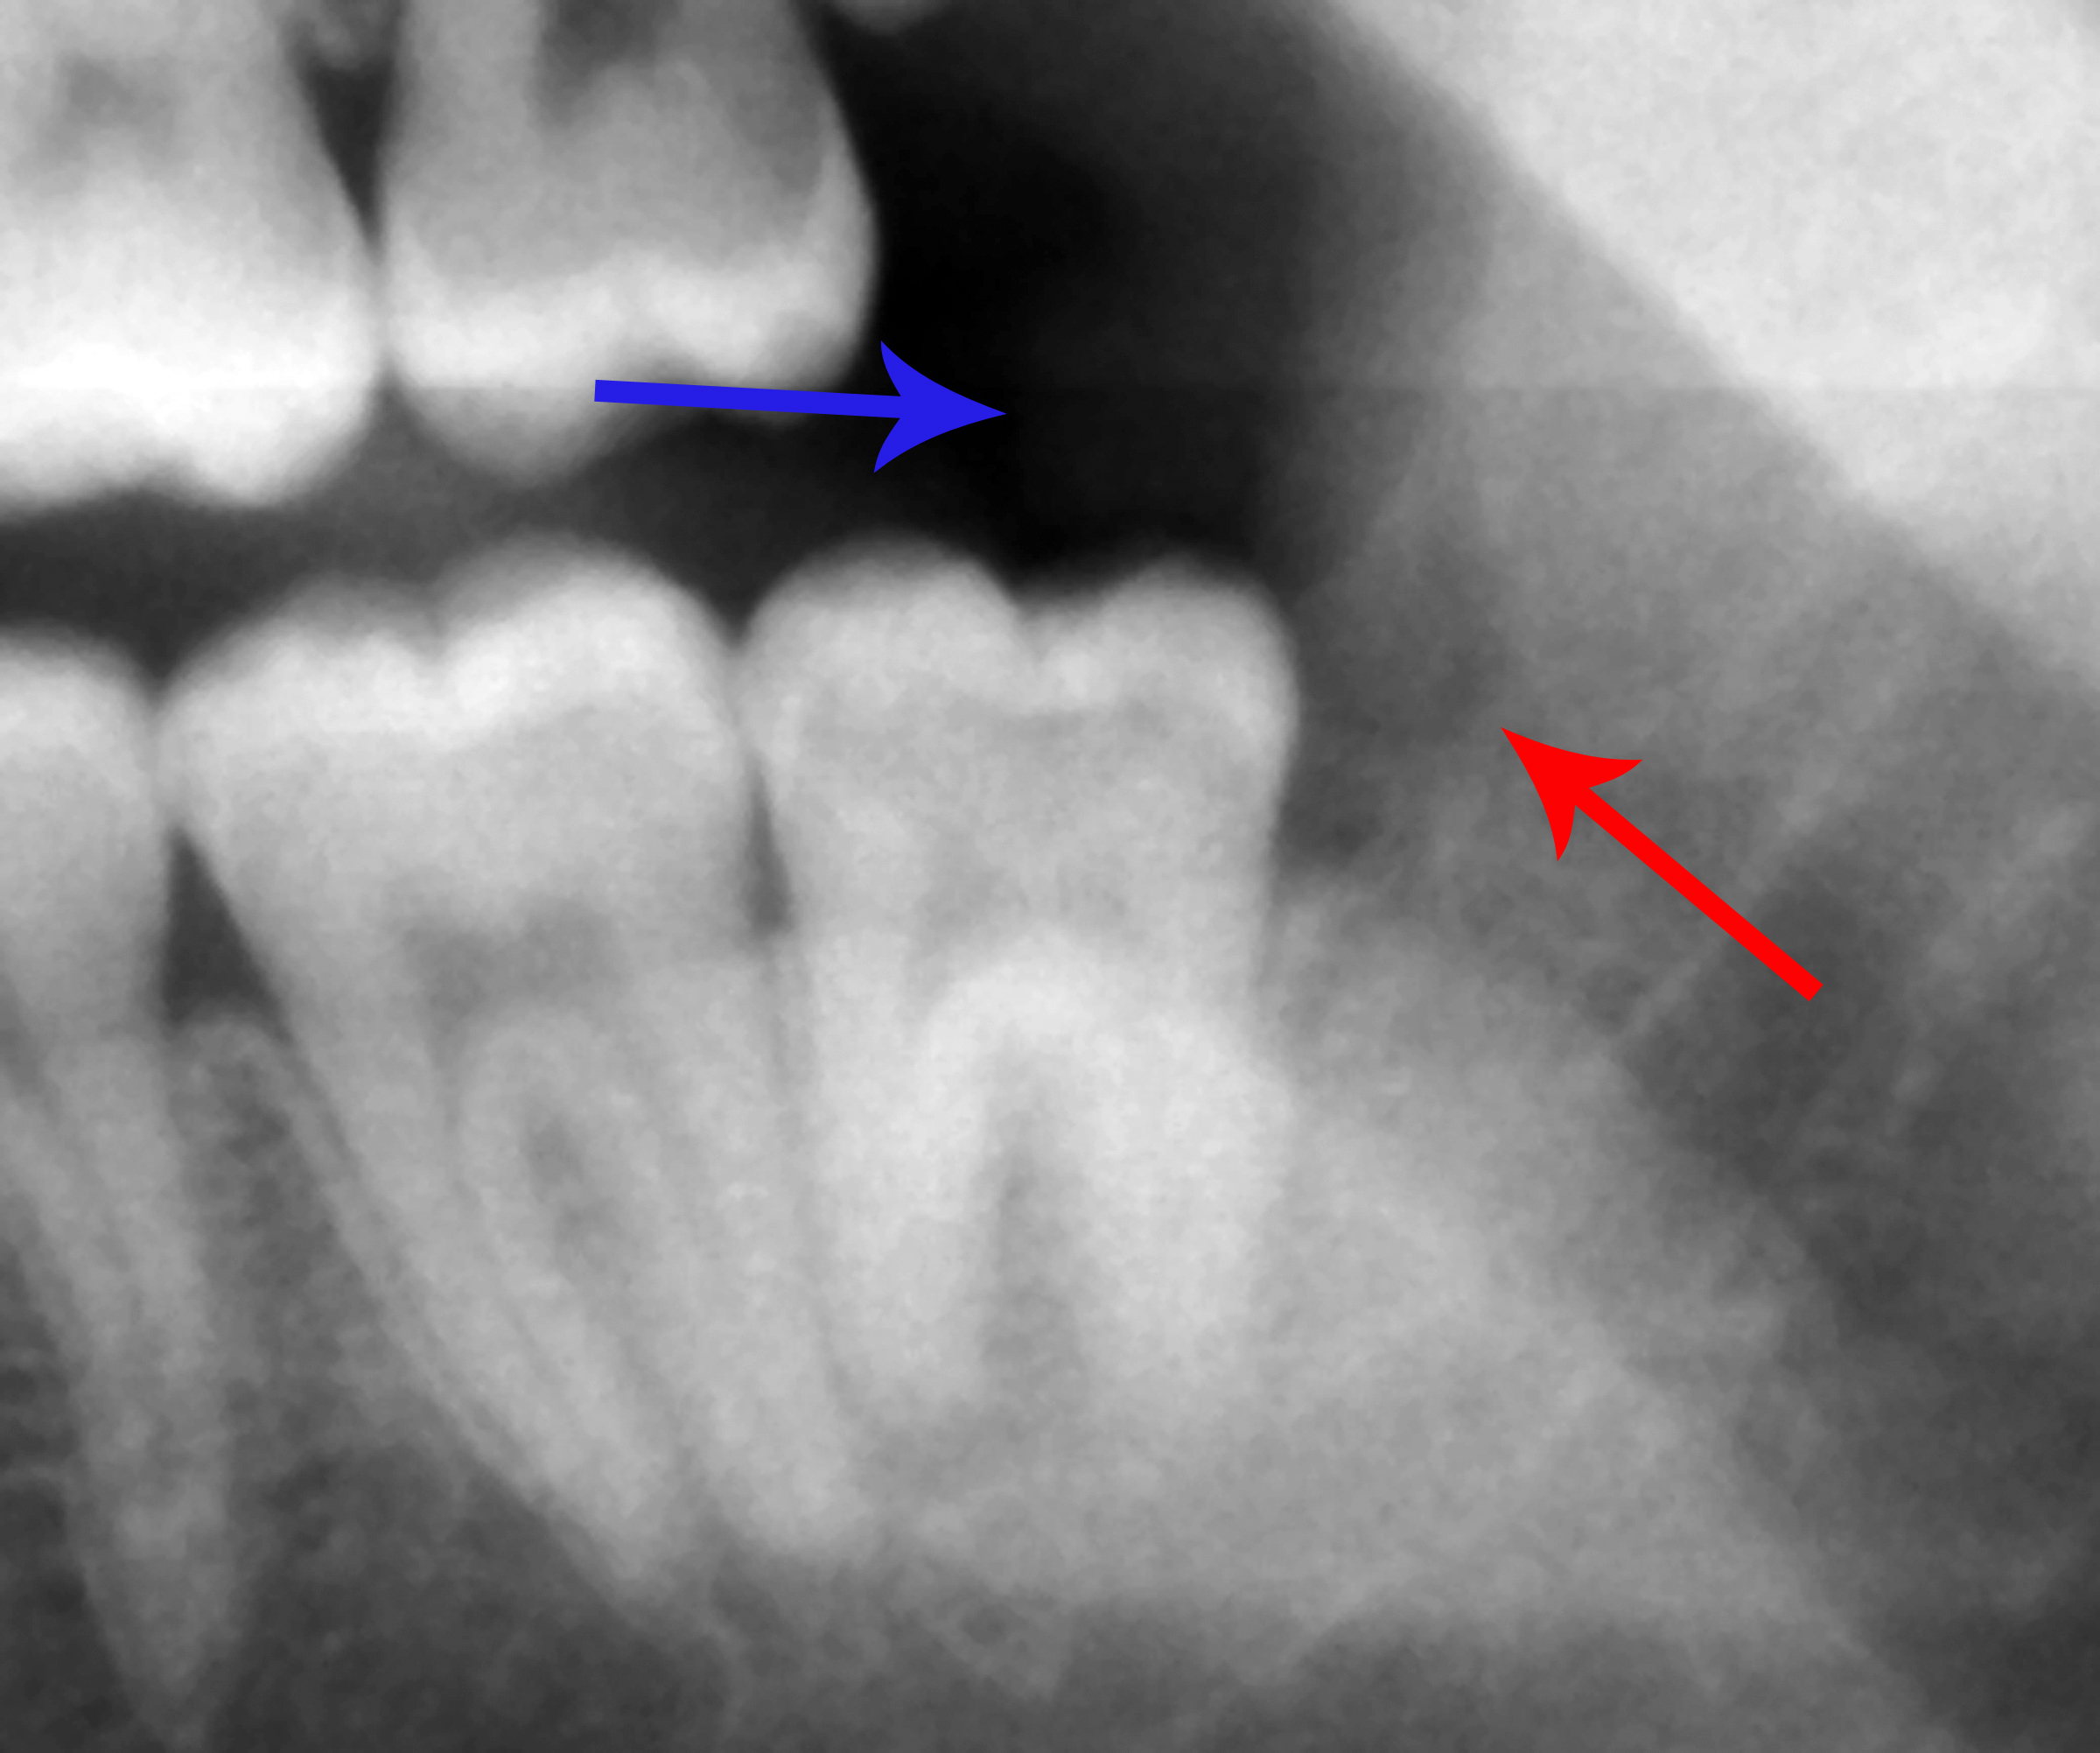

Een verstandskies die horizontaal geïmpacteerd was. De verstandskies (vooral gebruikelijk in Nederland) of wijsheidstand (algemeen Vlaams) [1] is een gebitselement bij de mens. Deze bevindt zich direct achter de tweede molaar en wordt dan ook wel de "derde molaar" genoemd. In een normaal gebit is het de achtste tand vanaf het midden van de.

Rond de leeftijd van 5 à 6 jaar beginnen de verstandskiezen in het tandvlees te vormen. Echter is dit op een orthopantomogram (röntgenfoto van de kaak) niet altijd zichtbaar. Meestal kunnen ze pas op de leeftijd van 10 à 11 jaar met een röntgenfoto worden gelokaliseerd. Het proces van doorkomende verstandskiezen verschilt van persoon tot.

Dit kunnen je verstandskiezen zijn die proberen door te breken. Let op rood, gezwollen tandvlees aan de achterkant van je kaak, waardoor kauwen moeilijk of ongemakkelijk wordt. Controleer of je tanden beginnen te draaien of scheef gaan staan. Dit kunnen je verstandskiezen zijn die je andere tanden verdringen. Deel 1.

Symptomen van problemen aan de verstandskiezen. In sommige gevallen veroorzaken getroffen verstandskiezen wel problemen. Misschien ervaar je roodheid en zwelling rond het gebied van de getroffen kies, en pijn aan de kaak, hoofdpijn of een vreemde smaak als je op het gebied in de buurt van de getroffen tand bijt.